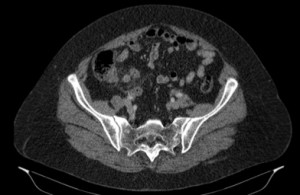

Caso 28

Francisco Martínez Pacheco